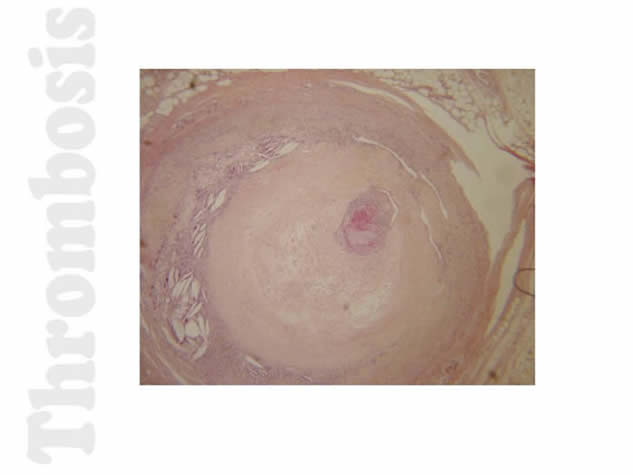

Thrombosis